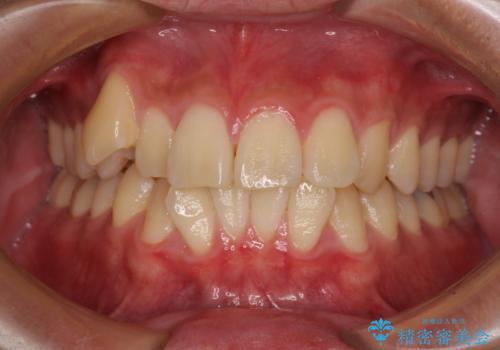

- 前歯のデコボコと右上の八重歯を気にして来院された患者様です。

マウスピース矯正とワイヤー矯正で悩んでいらっしゃいましたが、非常に強い咬合力であることや、お仕事柄不規則な生活リズムになることが多いとのことで、ワイヤー装置にて矯正治療を行うこととしました。